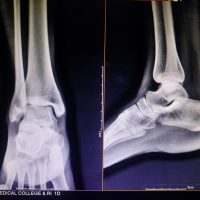

Figure 1: Left Humerus X-ray. (a) Anteroposterior X-ray of left humerus upon initial presentation to orthopedic clinic. (b) Lateral X-ray of left humerus several hours after surgical fixation, 2 weeks after image 1a. (c) Lateral X-ray of left humerus 6 months after surgical fixation. (d) Anteroposterior X-ray of the chest, including the left proximal to midshaft humerus, 1.5 years after surgical fixation. (e) Lateral X-ray of the left elbow, 1 year and 4 months after surgical fixation.

The surgery was successful, and the patient recovered well, reporting minimal pain with improvements in strength and motion in the left shoulder and elbow. Post-operative imaging, as shown in Fig. 1b, demonstrated increased bony callus at the fracture site, and the patient was instructed to continue load-bearing as tolerated for activities of daily living. One month following surgery, the patient began chemotherapy with intravenous nivolumab every 14 days and oral cabozantinib 40 mg daily. She tolerated the chemotherapy well, without any adverse reactions. At 6 months (Fig. 1c) and more than 1½ years later, the patient is doing very well in regard to the procedure, reporting good strength and motion in her left shoulder and elbow, with minimal pain. She continues weight-bearing as tolerated, and her overall recovery has been positive while she still undergoes treatment for metastatic RCC (Fig. 1d and e).